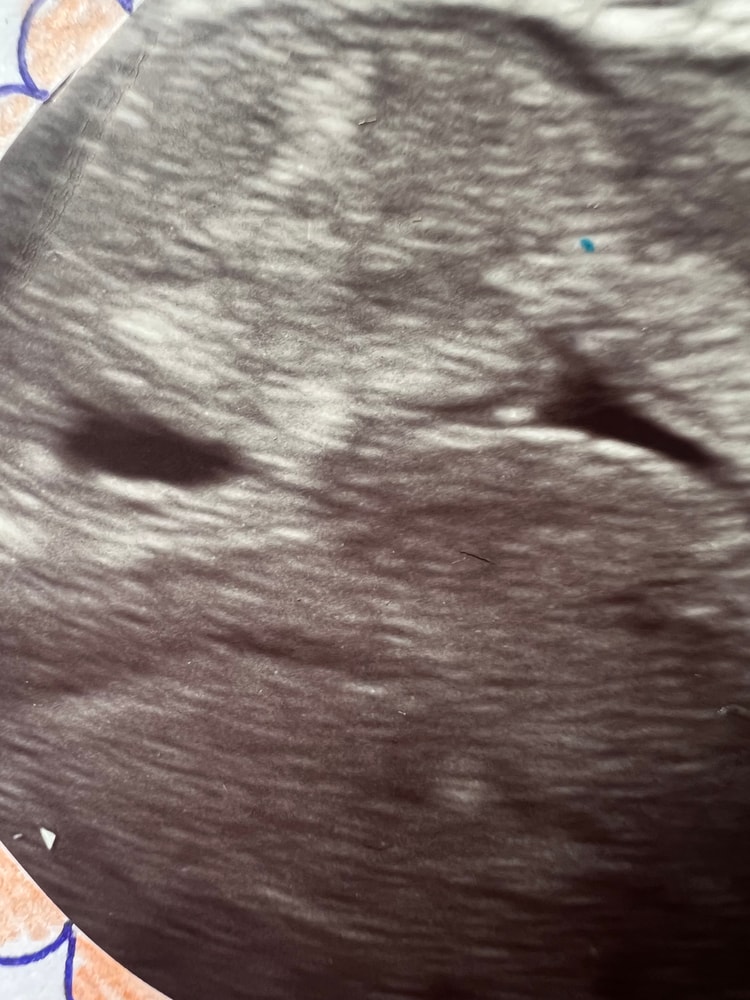

Двое? Посмотрите узи кто может, нам 6 недель

Два 100%)) Третий под вопросом))

07.02.2014

А что между ними? Я вижу три)))

06.02.2014

Вот и я тоже вижу три, но Г третий даже не прокомментировал. Во время просмотра этого третьего было не видно он как то проявился в момент снимка )))